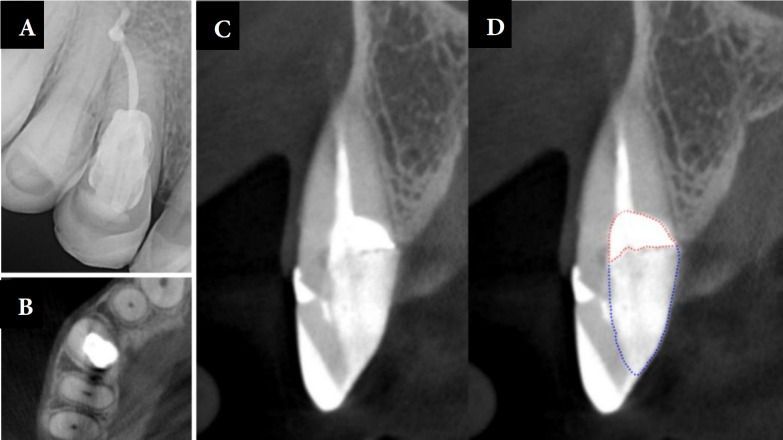

External cervical resorption is a condition that leads to the loss of hard dental tissues, including enamel, cementum, and dentin. Although it is an aggressive condition, its causes are not yet fully understood. The treatment of resorptions depends on their extent, location and the material used. When managing these lesions, the position of the bone crest and the ability of the periodontal tissue to adhere to the material after setting must be considered. This case report aims to demonstrate a clinical case of external cervical resorption which was treated by a proposed protocol that uses different dentin substitute restorative materials depending on the location of the resorptive area in relation to the bone crest. The success of this treatment depended on the correct use of materials and adequate tissue management. The combination of different materials has shown promising results in treating resorptions in both supra- and infra-osseous areas.